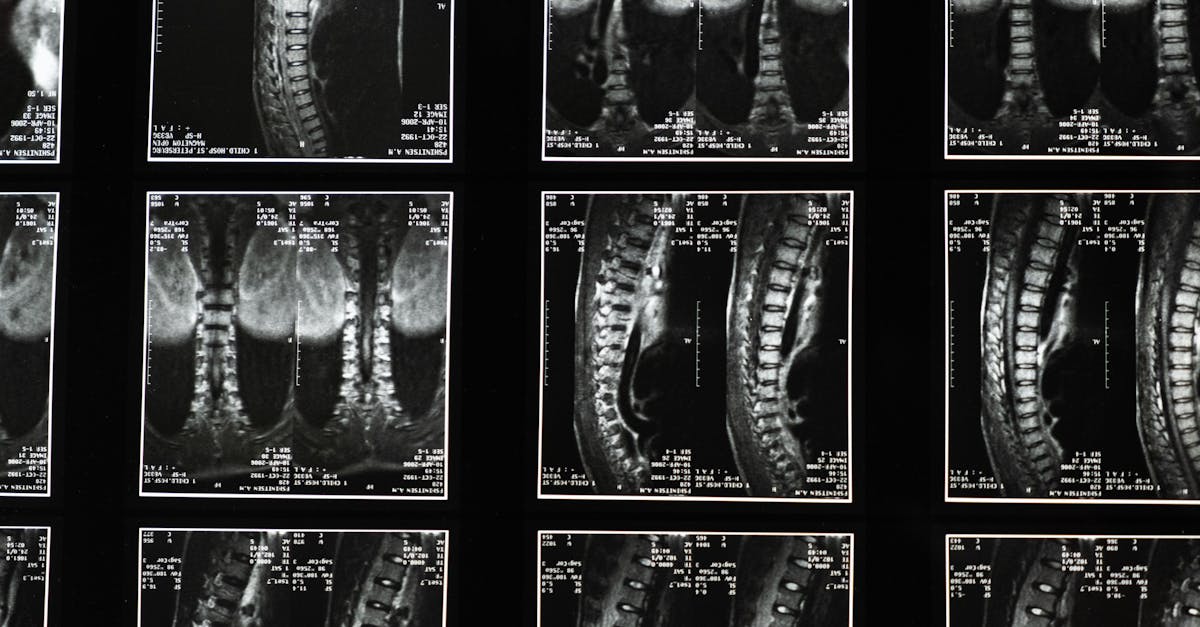

La décompression neurovertébrale est une technique qui vise à relâcher les tensions présentes dans la colonne vertébrale. En étirant doucement la colonne, elle aide à soulager les douleurs associées à des problèmes tels que les hernies discales, les bombements discaux ou la dégénérescence discale. Cette méthode a pour objectif de favoriser la guérison naturelle des tissus et à augmenter l’espace entre les vertèbres, ce qui peut améliorer la circulation sanguine.

Mécanisme d’Action de la Décompression Neurovertébrale

La décompression neurovertébrale fonctionne grâce à l’application d’une traction contrôlée sur la colonne vertébrale. Cette technique vise à augmenter l’espace entre les disques intervertébraux, réduisant ainsi la pression sur les nerfs et les tissus environnants. En diminuant cette pression, la méthode favorise la circulation sanguine, ce qui peut à son tour accélérer le processus de guérison des tissus endommagés. De plus, cette réduction de la pression contribue à améliorer l’hydratation des disques, favorisant leur santé à long terme.

En appliquant une force de traction modérée et sérieuse, la décompression neurovertébrale vise à restaurer l’espace intervertébral. Cela permet non seulement de soulager la douleur, mais aussi de favoriser la guérison naturelle des disques endommagés souvent impliqués dans des conditions telles que les hernies discales ou les discopathies. La technique agit en douceur, facilitant ainsi l’amélioration de la circulation sanguine dans la région affectée, ce qui contribue à une réduction significative des symptômes.